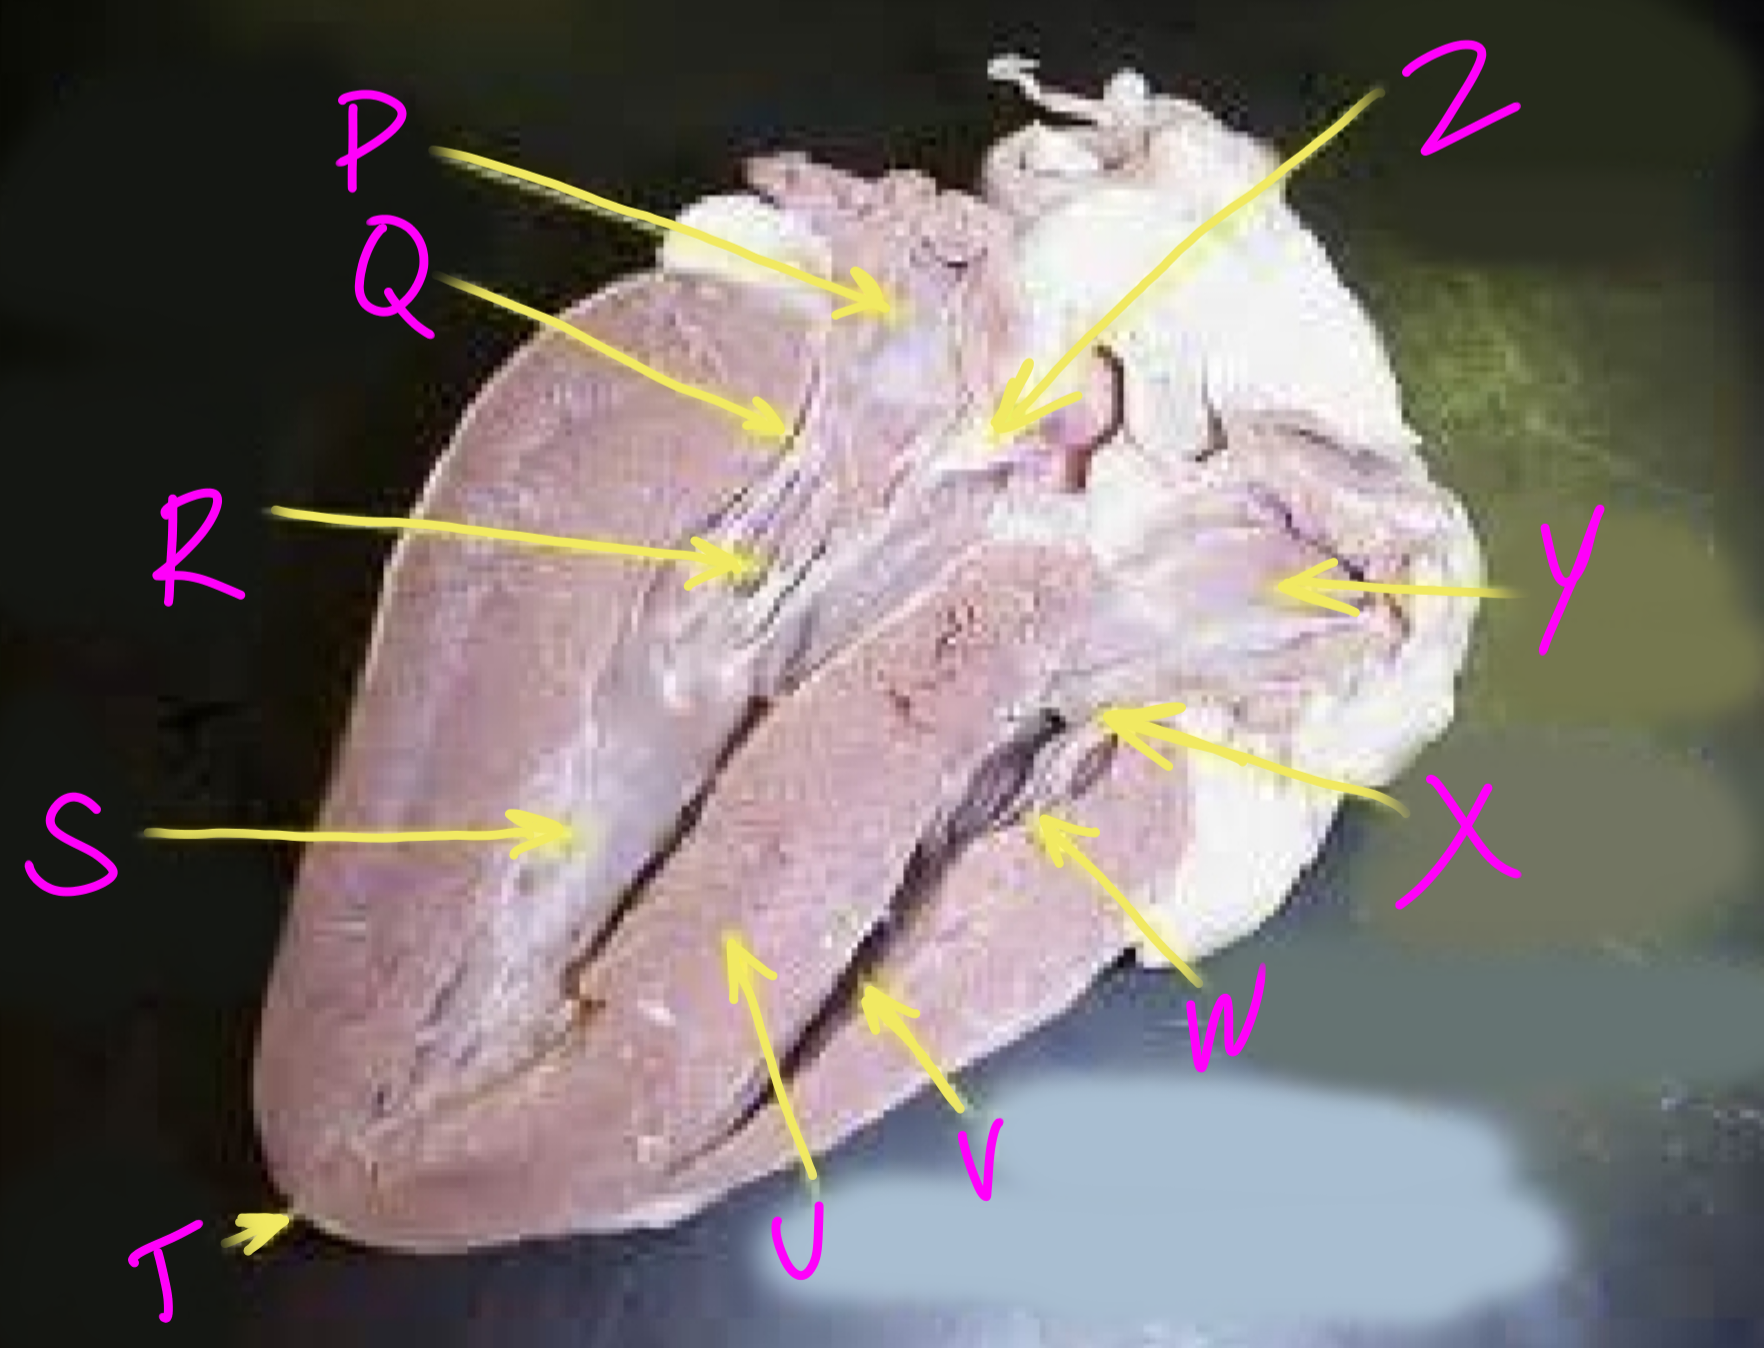

P

Left atrium

Q

Bicuspid valve - allows blood to flow from the left ventricle to the aorta

R

Right chordae tendinae - hold AV valves in place

S

Left ventricle

T

Apex - pumps blood out of the ventricles

U

Interventricular septum - divides the right and left ventricles

V

Right ventricle

W

Left chordae tendinae - hold AV valves in place

X

Tricuspid valve

Y

Right atrium

Z

Aortic semilunar valve - prevent backflow